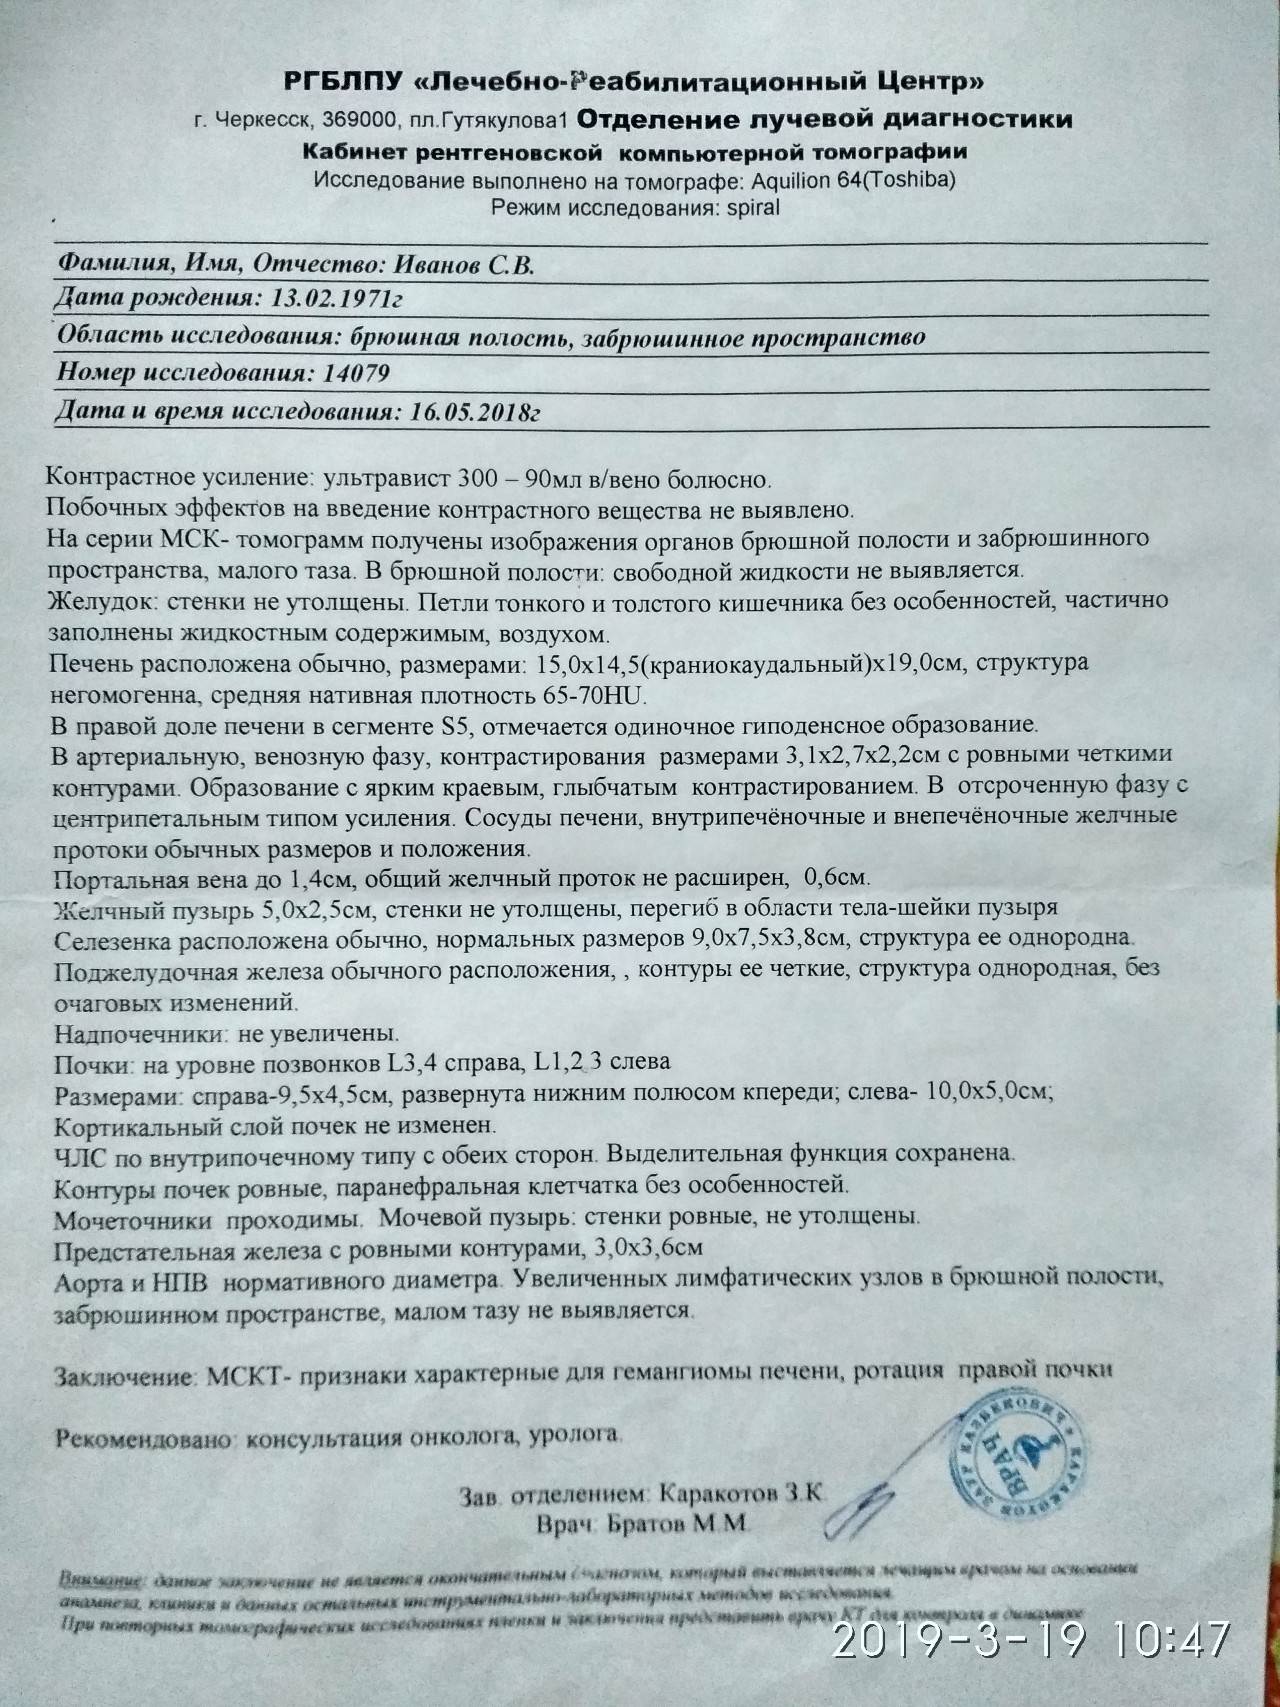

СКТ ОБП

Малый таз с контрастированием кт